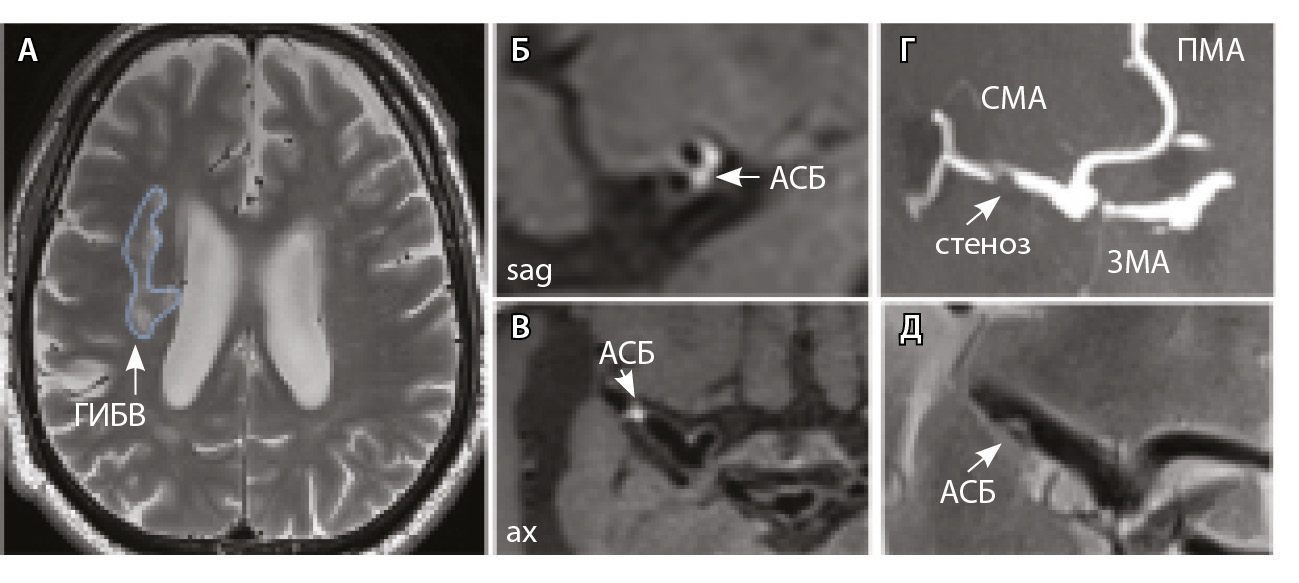

Рис. 4. Пациент К., 69 лет, с признаками церебральной микроангиопатии (F2 по шкале Fazekas) и атеросклерозом интракраниальных артерий, с формированием гемодинамически значимого стеноза в сегменте М1 правой средней мозговой артерии (СМА): А – магнитно-резонансная томография (МРТ), режим Т2-взвешенного изображения: видны множественные сливные очаги гиперинтенсивности белого вещества (ГИБВ); Б, В – МРТ сосудистой стенки, режим T1-TSE-db-FS после контрастного усиления: в сегменте М1 правой СМА визуализируется эксцентричная атеросклеротическая бляшка (АСБ), интенсивно накапливающая контрастный препарат; Г – трехмерная магнитно-резонансная времяпролетная (3D ToF) ангиография: виден стеноз правой СМА в сегменте М1; Д – режим HR Т2-TSE: видна АСБ в сегменте М1 правой СМА; ax – аксиальная, sag – сагиттальная плоскости; ЗМА – задняя мозговая артерия; ПМА – передняя мозговая артерия